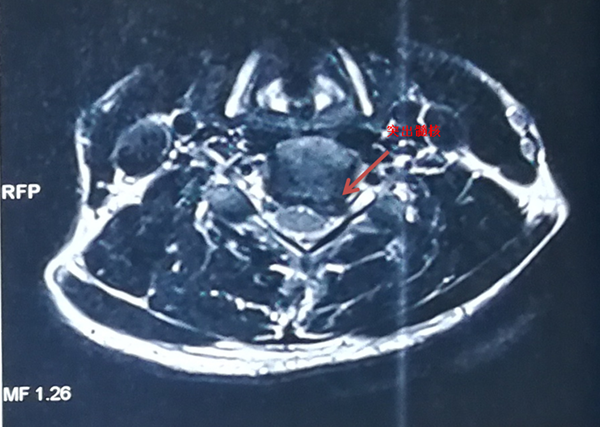

手术前MRI